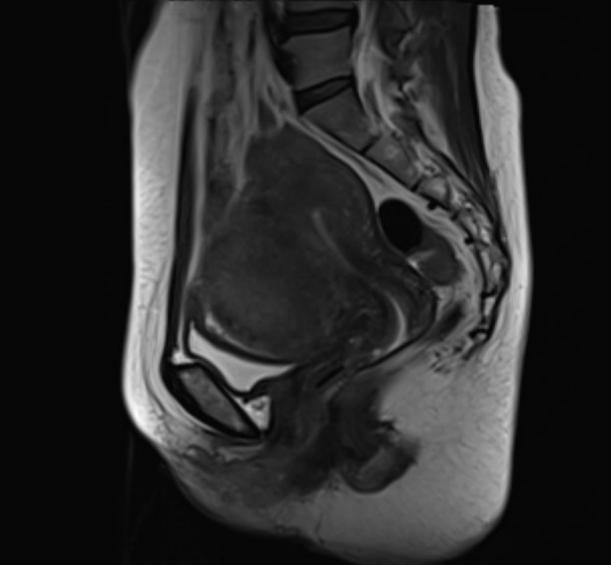

确定好手术时间后,盛女士在家人陪同下提前入住我院妇产科。经入院彩超检查和盆腔MRI平扫提示,子宫肌瘤直径达到了8cm,已经压迫膀胱,需尽快手术。